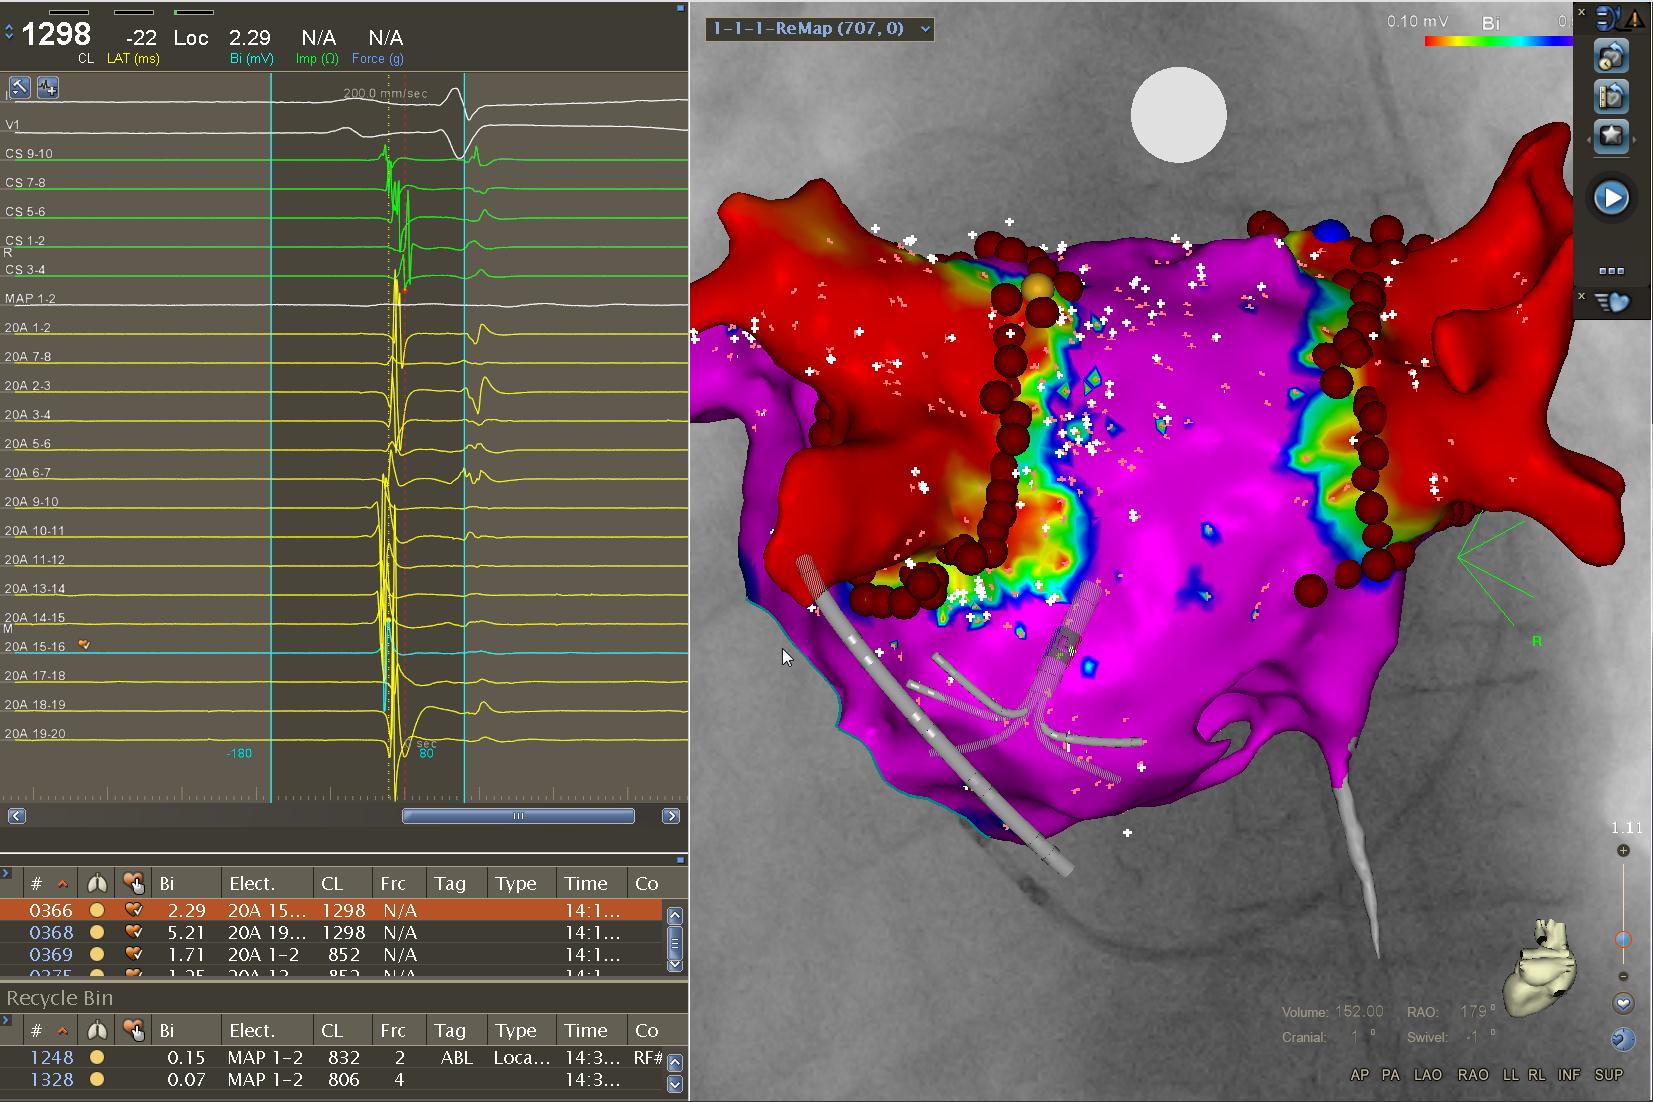

心律失常团队通过近十年的探索,结合国际先进经验及最新研究独创湘雅三医院的房颤术式(高密度标测指导下BOX+基质改良术,HOT术式),该术式大大提高了持续性房颤的手术成功率,并已启动全球随机多中心研究。